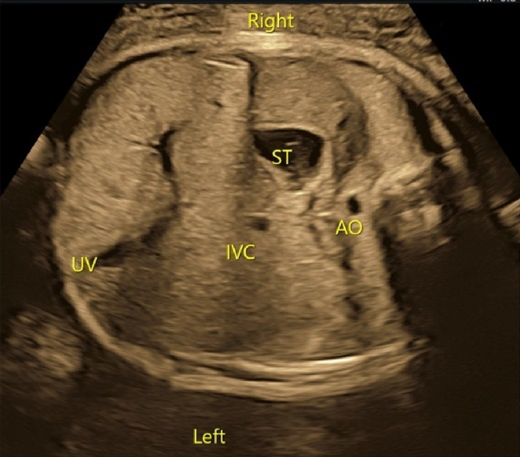

(1) Abdominal Cross-Section

The laterality of the fetus must be determined unequivocally. The gastric bubble is to be found on the left side of the body, the aorta on the left of the spinal column, and the inferior vena cava on the right. The inferior vena cava should be connected to the right atrium. Abnormal relationship between these structures is often the case in heterotaxy syndrome. Total anomalous pulmonary venous return of an infracardiac type may present an abnormal blood vessel (a vertical vein) in the abdominal cross-section.